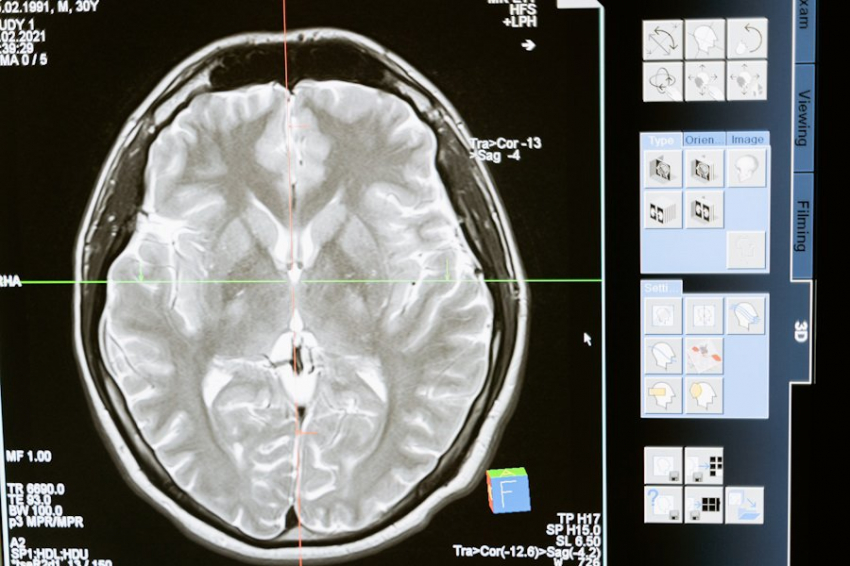

Современные методы визуализации, такие как МРТ и ПЭТ, позволяют ученым наблюдать за активностью мозга в реальном времени. Эти исследования наглядно демонстрируют, что даже при выполнении простейших задач задействуются различные области мозга, работающие в сложном взаимодействии.